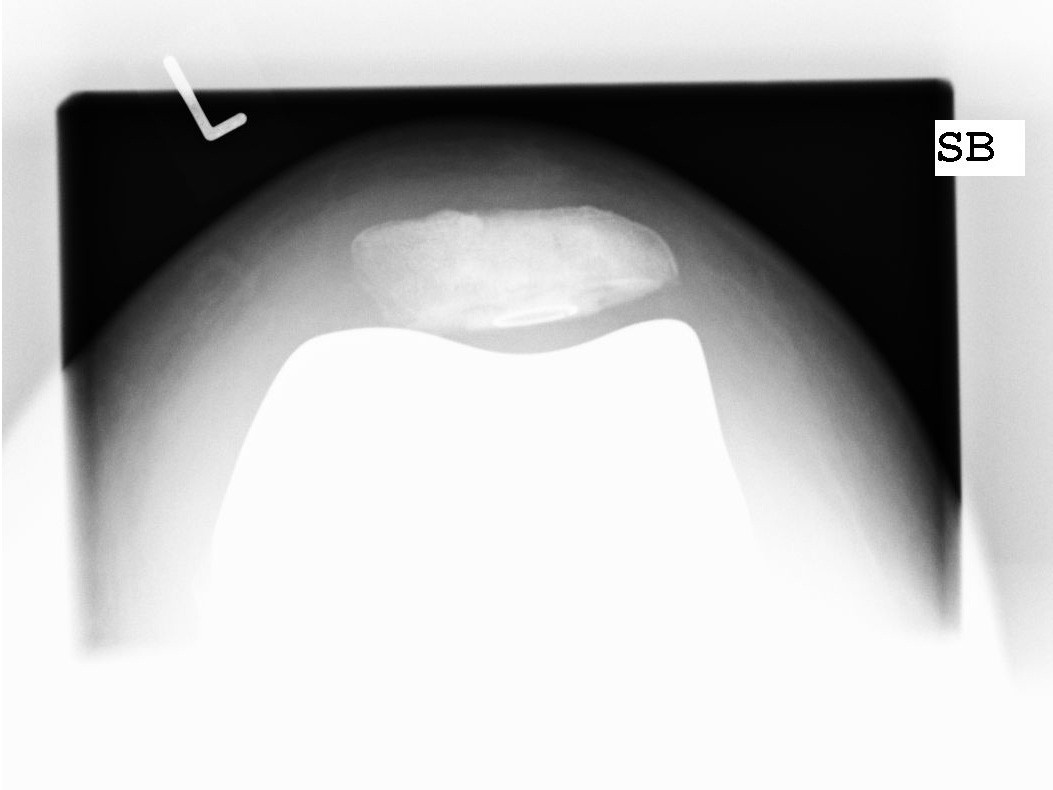

Teilgelenkersatz des Kniescheibengleitlagers („Femoropatellarersatz“)

Bei vielen Patienten ist nur der Anteil hinter der Kniescheibe von einem fortgeschrittenen Verschleiß betroffen. Hier gibt es die Möglichkeit einen Ersatz dieser Gelenkflächen hinter der Kniescheibe und korrespondierend dazu das Gleitlager für die Kniescheibe am Oberschenkel zu ersetzen. Hierbei bleiben sämtliche Bänder, Menisken sowie der innere und äußere Gelenkanteil intakt.

Ersatz der Kniescheibenrückfläche

In manchen Fällen entwickelt sich nach Ersatz des Kniegelenkes ein Schmerzsyndrom hinter der Kniescheibe z.B. durch einen fortschreitenden Verschleiß in diesem Bereich. Hier wird dann der isolierte Ersatz der Kniescheibenrückfläche empfohlen.